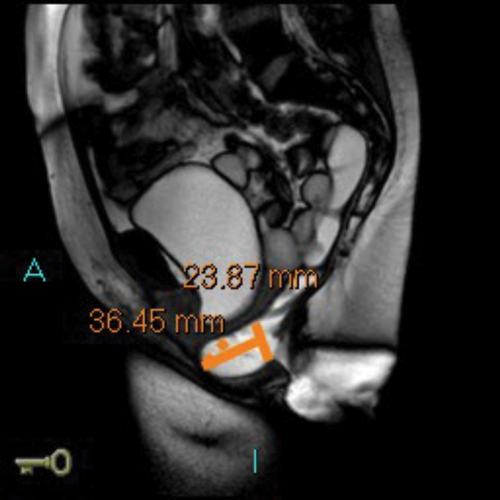

MR defecating proctograms are performed in a 1.5 Tesla MR scanner (Philips Sense). A similar detailed explanation of the procedure and consenting process takes place, so the patient knows what to expect during the three ‘cine’ scans of ‘squeeze up’, ‘bear down’ and ‘empty out’. The urinary bladder must be empty as far as possible during the MR scan.

After an initial digital rectal examination, 120mls of ultrasound jelly is instilled into the rectum via a rectal tube with the patient in the left lateral position. The patient is then turned to lie supine and positioned so that the top of the Sense-body coil is at same level with the iliac crest. The MRI scan protocol includes T2 axial and coronal sequences and sagittal ‘cines’ squeeze, bear down and two defecatory attempts with a couple of minutes rest in between. In cases of incomplete evacuation, a repeat evacuation may be needed or a coronal cine.

In addition the anterior and middle compartment is assessed, particularly for the presence and anatomy of a cystocoele or vault prolapse. The T2 sequences also allow pelvic evaluation for other incidental pathologies (Figure 2).

Figure 2a: Baseline MR proctogram.

Figure 2b: Pelvic floor descent MR proctogram.

Figure 2c: Large cystocoele MR proctogram.

Figure 2d: Large rectocoele on MR proctogram.